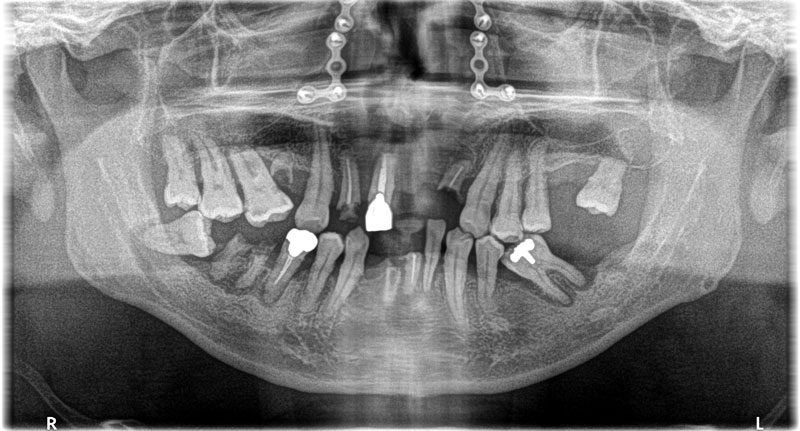

- 上下のCT解析を行う。(上顎には以前の顔面骨折による治療跡であるチタンのプレート、ボルトが確認できる。左側は慢性の副鼻腔炎を患っている。)

- 上顎、鎮静、局所麻酔下で抜歯即時埋入6本、傾斜埋入1本行う。(鼻中湾曲を認め、左側は重度の慢性副鼻腔炎もわずらっていたため、ソケットリフトやサイナスリフト等の副鼻腔へのアプローチは回避した。)

- 下顎、鎮静、伝達局所麻酔下で抜歯即時埋入6本を行う。

- 3か月後インプラントが骨に定着したのを確認し(ISQ値75以上)、一時的に使用していた残存歯を抜歯、ソケットプリザベーションし、インプラントによる仮歯を装着。